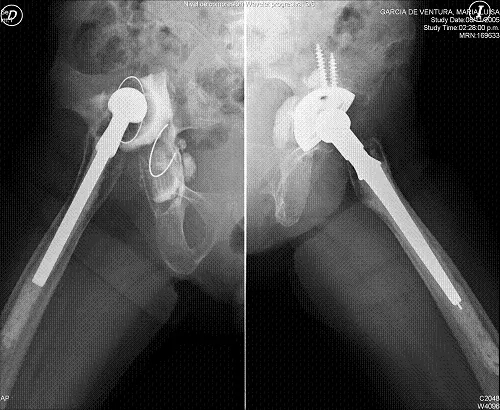

The head and femoral neck resection technique was described by Girdlestone in 1920 as a palliative treatment in patients with hip tuberculosis. This name is still used today to designate the removal of hip prostheses with cement and the regularization of the proximal portion of the remaining femur, when removal is required.

The complications that most frequently force this surgery are hip infections which, despite having decreased their incidence from 9.5% of the first prostheses of the sixties to values between 0.6% and 2.3% of the nineties, are a serious medical and economic problem. Other less frequent complications, but which may also require a Girdlestone intervention, are periprosthetic fractures, recurrent dislocations or the need for multiple hip arthroplasty replacements in poor quality bone. In these cases it remains a valid option to try to alleviate pain or improve the functional situation of patients.

The treatment of choice in an infected prosthesis is two-stage replacement; surgical cleaning of all elements, including cement; antibiotic treatment for a variable period depending on the germ and, subsequently, placement of a new prosthesis. However, in elderly patients with a poor clinical situation this alternative may involve more risks than benefits.